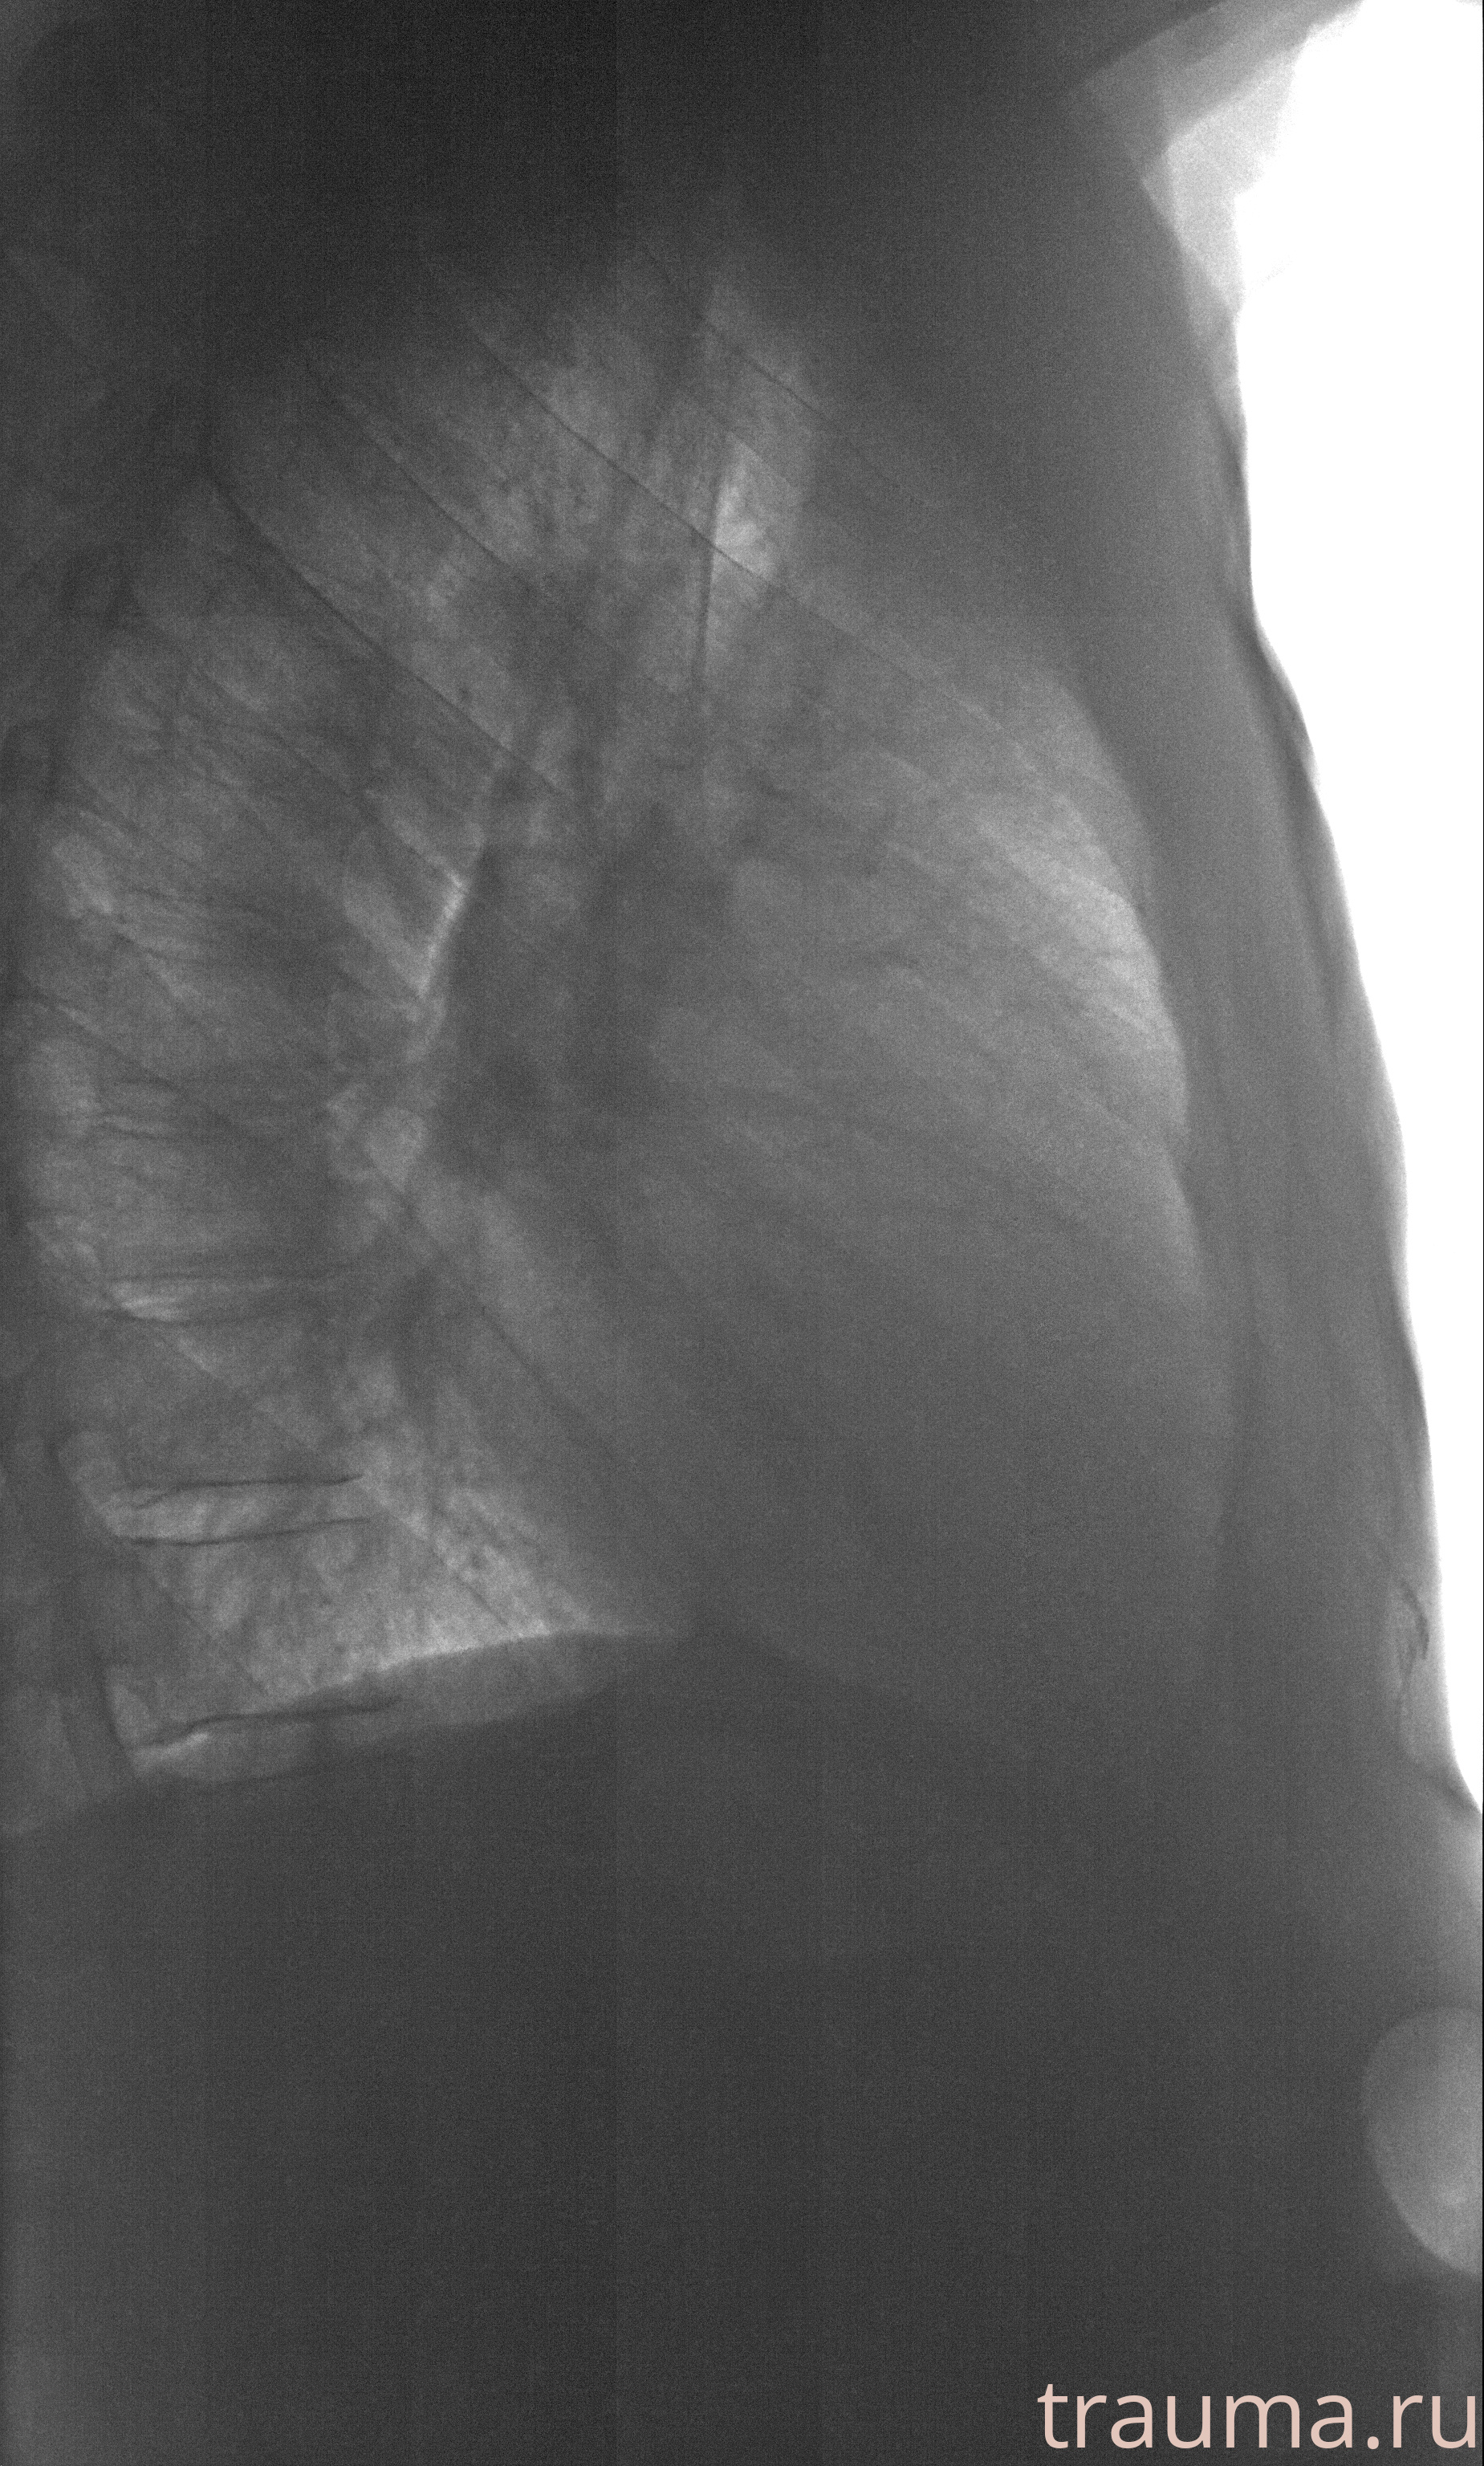

Рентгенограммы

Рентген на дому: по вашему адресу приезжает врач-рентгенолог, травматолог-ортопед с мобильным рентгеновским аппаратом, проводит диагностику травмы или заболевания, делает необходимые рентгенограммы, дает рекомендации по дальнейшему лечению. Получить качественные снимки в домашних условиях возможно благодаря уникальной методике, разработанной МосРентген Центром для института  Склифосовского

Яркость: 1   Контраст: 1   Инвертировать: 0 Увеличение: 1

Перетаскивайте мышь вверх/вниз для контраста, влево/право для яркости. Прокрутка колесом изменяет масштаб. Нажмите Сбросить для возврата к исходному изображению. При увеличении держите мышь в той области, которую хотите рассмотреть.